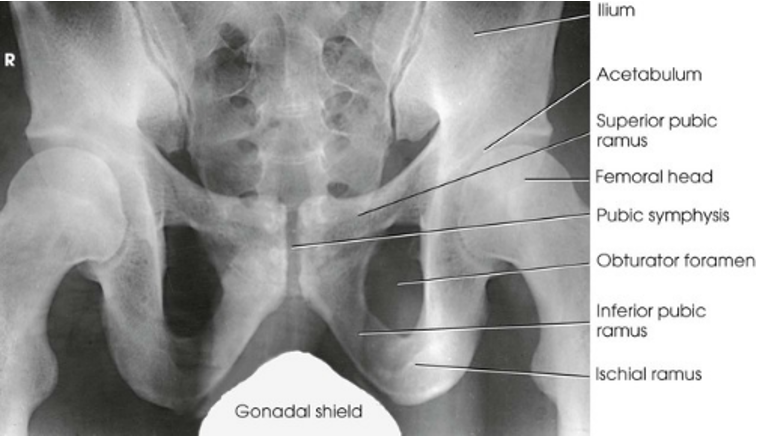

AP Projection; Pelvis and Proximal Femora

AP Projection; Pelvis and Proximal Femora (Labeled)